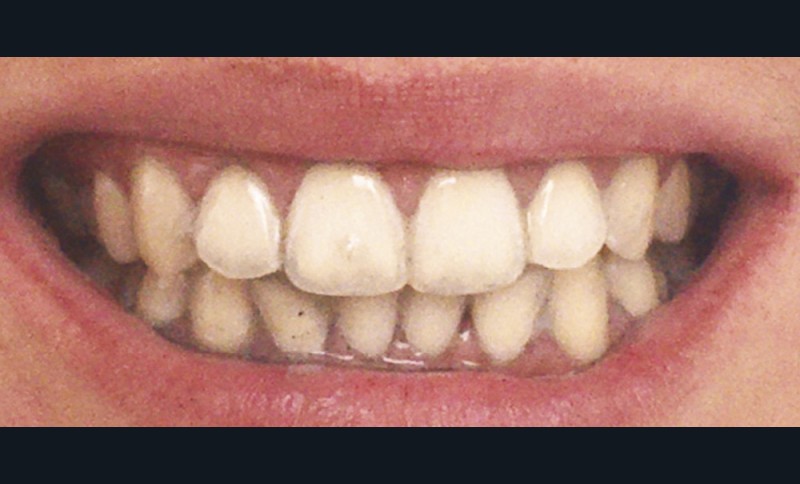

À l’heure où les ingrédients naturels sont en vogue, les produits à base de charbon végétal se sont fait une place dans les rayons cosmétiques et ceux des parapharmacies (masques, shampoings…). Et les dentifrices n’ont pas échappé à cette nouvelle tendance ! Tous ces produits vantent l’effet « blanchissant » et leurs avantages pour l’hygiène dentaire en général. Cependant, la capacité blanchissante et autres propriétés des dentifrices au charbon sont scientifiquement largement mises en doute. Au contraire, ces produits favoriseraient les caries dentaires et, à long terme, pourraient induire des effets nocifs sur les dents et les tissus parodontaux (colorations, abrasion…) [18].

Brooks et al. en 2017 [19] ont publié une revue de la littérature à partir de 118 articles et d’une base de données de cinquante dentifrices au charbon sur l’efficacité et la sûreté de ces produits. Leur première conclusion est alarmante : seulement 8 % de ces dentifrices contenaient du fluor. Et parmi ces derniers, les fluorures étaient peu ou pas efficaces pour lutter contre l’apparition de lésions carieuses. Le charbon, en raison de son fort pouvoir adsorbant, pourrait, au moins en partie, adsorber le fluor et réduire son action carioprotectrice. Les dentifrices au charbon végétal testés se voulaient « détoxifiants », « antibactériens » et « antifongiques » ; aucun de ces effets n’a pu être démontré dans la littérature, ne s’agissant que d’arguments marketing sans preuves scientifiques. 96 % des dentifrices promouvaient un effet blanchissant tout en étant peu abrasifs. Les dentifrices dits blanchissants, incluant ceux à base de charbon, possèdent uniquement un effet sur les colorations extrinsèques dues aux habitudes quotidiennes (tabac, café, thé…) par action de polissage grâce aux substances abrasives qu’ils contiennent [20]. Plus un dentifrice est abrasif, plus il est efficace pour éliminer les taches extrinsèques, mais son utilisation peut aussi engendrer des lésions d’abrasion. Le degré d’abrasivité des pâtes de dentifrice doit conserver au maximum l’intégrité des tissus dentaires tout en gardant une action nettoyante. Les fabricants doivent choisir le meilleur compromis pouvoir polissant/abrasivité.

L’abrasivité d’un dentifrice est quantifiée par l’indice relatif d’abrasion de la dentine, ou RDA (Relative Dentin Abrasivity). Cet indice renseigne sur le pouvoir abrasif d’un dentifrice en le comparant, en laboratoire, avec un témoin de référence dont l’indice est fixé à 100. Selon la norme ISO 11609, la RDA d’un dentifrice ne doit pas dépasser 250 (tableau 1). Entre 70 et 100, il est considéré comme moyennement abrasif, et dangereux pour la dentine et le cément. La réglementation en vigueur n’oblige pas les fabricants à mentionner la RDA sur les emballages des dentifrices. 96 % des dentifrices testés dans l’étude de Brooks et al. vantaient un effet peu abrasif, or un seul possédait un indice RDA faible [20].

Lors du brossage avec un dentifrice ou une poudre à base de charbon actif, il se crée une mousse gris noire, parfois difficile à éliminer. Des particules noires se déposent, et s’accumulent dans les sillons et anfractuosités des dents, au niveau des zones de jonctions des restaurations et au niveau de la gencive, laissant ainsi un liseré noir inesthétique (fig. 6). Pour supprimer ces colorations, un brossage plus long, plus actif, voire répétitif est souvent nécessaire (fig. 7 et 8).

Ainsi, en recherchant l’effet blanchissant, les utilisateurs de ces produits auraient également tendance à multiplier le nombre de brossages quotidien. Par conséquent, les lésions d’abrasion pourraient apparaître plus rapidement et/ou être accentuées. En effet, l’abrasivité ne dépend pas uniquement de l’agent abrasif, mais également de la technique et du nombre de brossages, de la dureté des poils de la brosse à dents, et de la fréquence d’utilisation des dentifrices dits « blanchissants ».